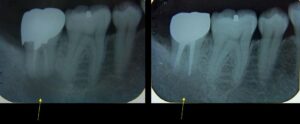

咬合研究会発表スライドの1枚

咬合研究会発表スライドの1枚